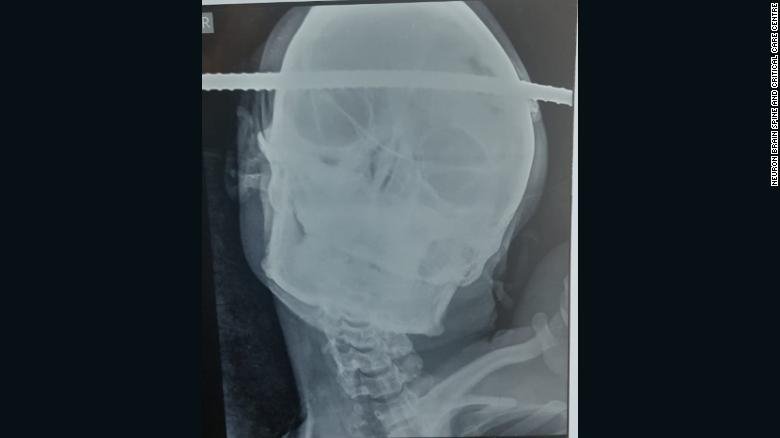

Ακτινογραφία που δείχνει λοστό να έχει τρυπήσει το κρανίο άνδρα

Η ακτινογραφία του λοστού, όπου διαπέρασε το κρανίου του εργάτη από την Ινδία / Φωτογραφία: Neuron Brain, Spine & Critical Care Center

Το σίδερο διαπέρασε το κρανίο από τη δεξιά πλευρά και εξήλθε από τον αριστερό μετωπιαίο λοβό. Ο 21 ετών εργάτης από την Ινδία ήταν τυχερός, καθώς το σιδερένιο αντικείμενο πέρασε ελάχιστα χιλιοστά έξω από κεντρική αρτηρία, ενώ δεν προκάλεσε καμία άλλη βλάβη στον εγκέφαλο.